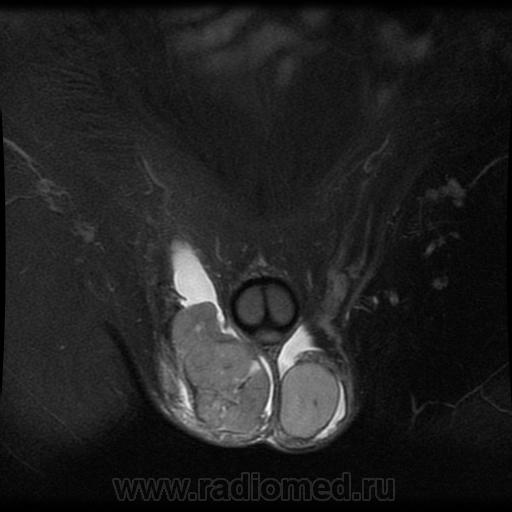

- https://radiomed.ru/sites/default/files/styles/case_slider_image/public/user/1/testis2-t2fs-ax.jpg?itok=I6c_v5AB

- https://radiomed.ru/sites/default/files/styles/case_slider_image/public/user/1/testis3-t2fs-ax.jpg?itok=hg7dh1HQ

"Мужчина, 60 лет. Около 3 месяцев назад появился дискомфорт в области мошонки, увеличение правого яичка."